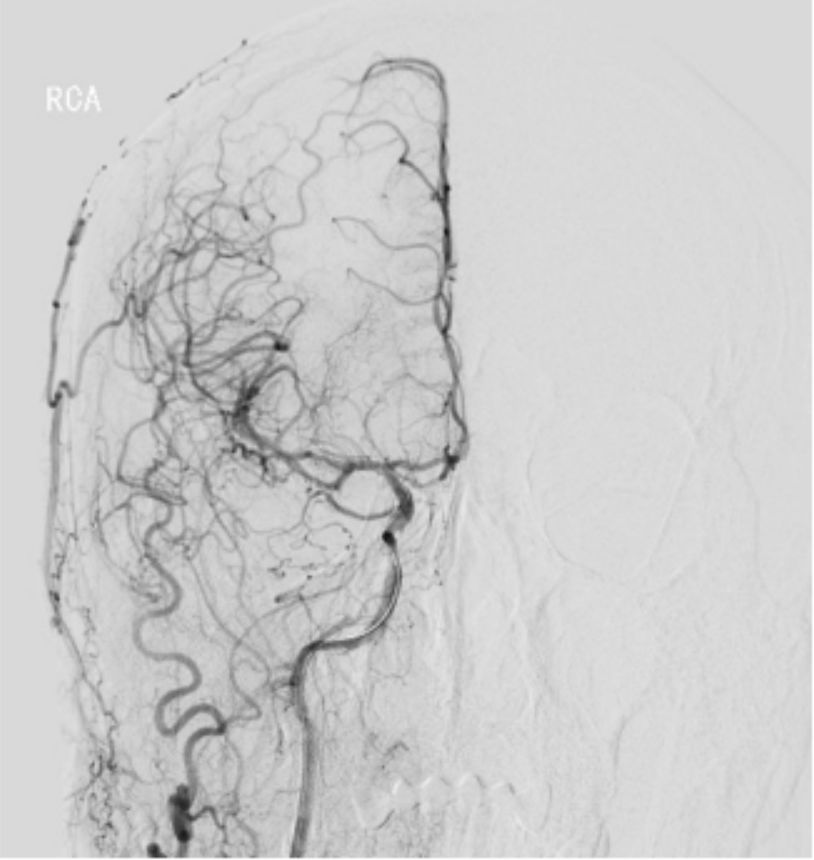

2019-06-07外院DSA:右侧颈内动脉闭塞(图2)。

图2

常规消毒铺巾,右侧股动脉穿刺成功,置入9F动脉鞘。150 cm超滑泥鳅导丝携5F单弯造影管分别行双侧颈总、左侧椎动脉正侧位造影,结果显示右侧颈内动脉C1-C4段闭塞,右侧颈外动脉侧枝向右侧眼动脉代偿供血,并反流至右侧颈内动脉颅内段,右侧大脑中、前动脉显影变淡(图5)。14∶50肝素4 000单位入壶,在长交换260 cm泥鳅导丝导引下将MOMA先端置于右侧颈外动脉,撤出泥鳅导丝。路径图下,PILOT50微导丝(0.014"x190 cm)携带Headway 21微导管沿MOMA送入右侧颈内动脉,微导丝通过闭塞段,微导管通过困难(图6)。

图5

此患者特点是右侧颈内动脉C1-C4段闭塞,右侧颈外动脉侧枝向右侧眼动脉代偿供血,并返流至右侧颈内动脉颅内段,向右侧大脑中、前动脉供血。手术过程中微导丝通过闭塞段,微导管通过闭塞段困难,撤微导管的过程中使用了球囊锚定技术固定微导丝。球扩时首先选择小球囊扩张狭窄段,然后根据造影情况逐步选用直径较大的球囊预扩,循序渐进开通血管,最后C1段置放WALLSTENT支架,残余段狭窄再次使用球囊扩张,视察10 min,行右侧颈总动脉正侧位造影,显示右侧大脑中、前动脉及分支动脉显影良好,开通手术成功。手术过程曲折,但结局良好。术后患者诉左侧肢体无力症状明显改善,远期疗效尚待视察随访。